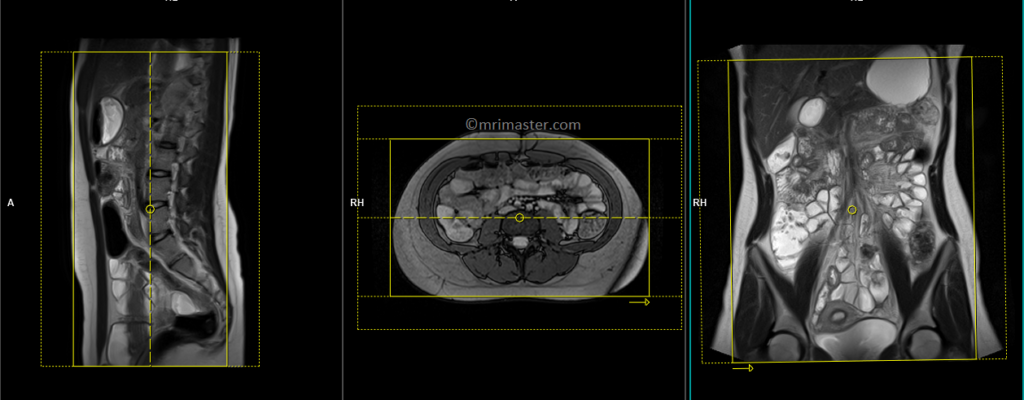

T2 TRUEFISP coronal 4mm

Plan the coronal slices on the axial image. Position the block horizontally across the abdomen as shown, and ensure that the positioning block is also checked in the other two planes. Establish an appropriate angle vertically across the abdomen in the sagittal plane. Make sure the slices adequately cover the entire abdomen, extending from the anterior abdominal wall to the erector spinae muscle. The field of view (FOV) should be large enough to encompass the abdomen and pelvis, ranging from the stomach to the pubic symphysis. To prevent wraparound artifacts, utilize phase oversampling. Instruct the patient to hold their breath during image acquisition. (In our department, we instruct the patients to breathe in and out twice before giving the “breathe in and hold” instruction.)

Protocol Parameters TRUEFISP coronal

TR 4-5 | TE 2-3 | FLIP 60 | NEX 1 | SLICE 4 MM | MATRIX 320×320 | FOV 400-450 | PHASE R>L | OVERSAMPLE 50% | IPAT OFF |